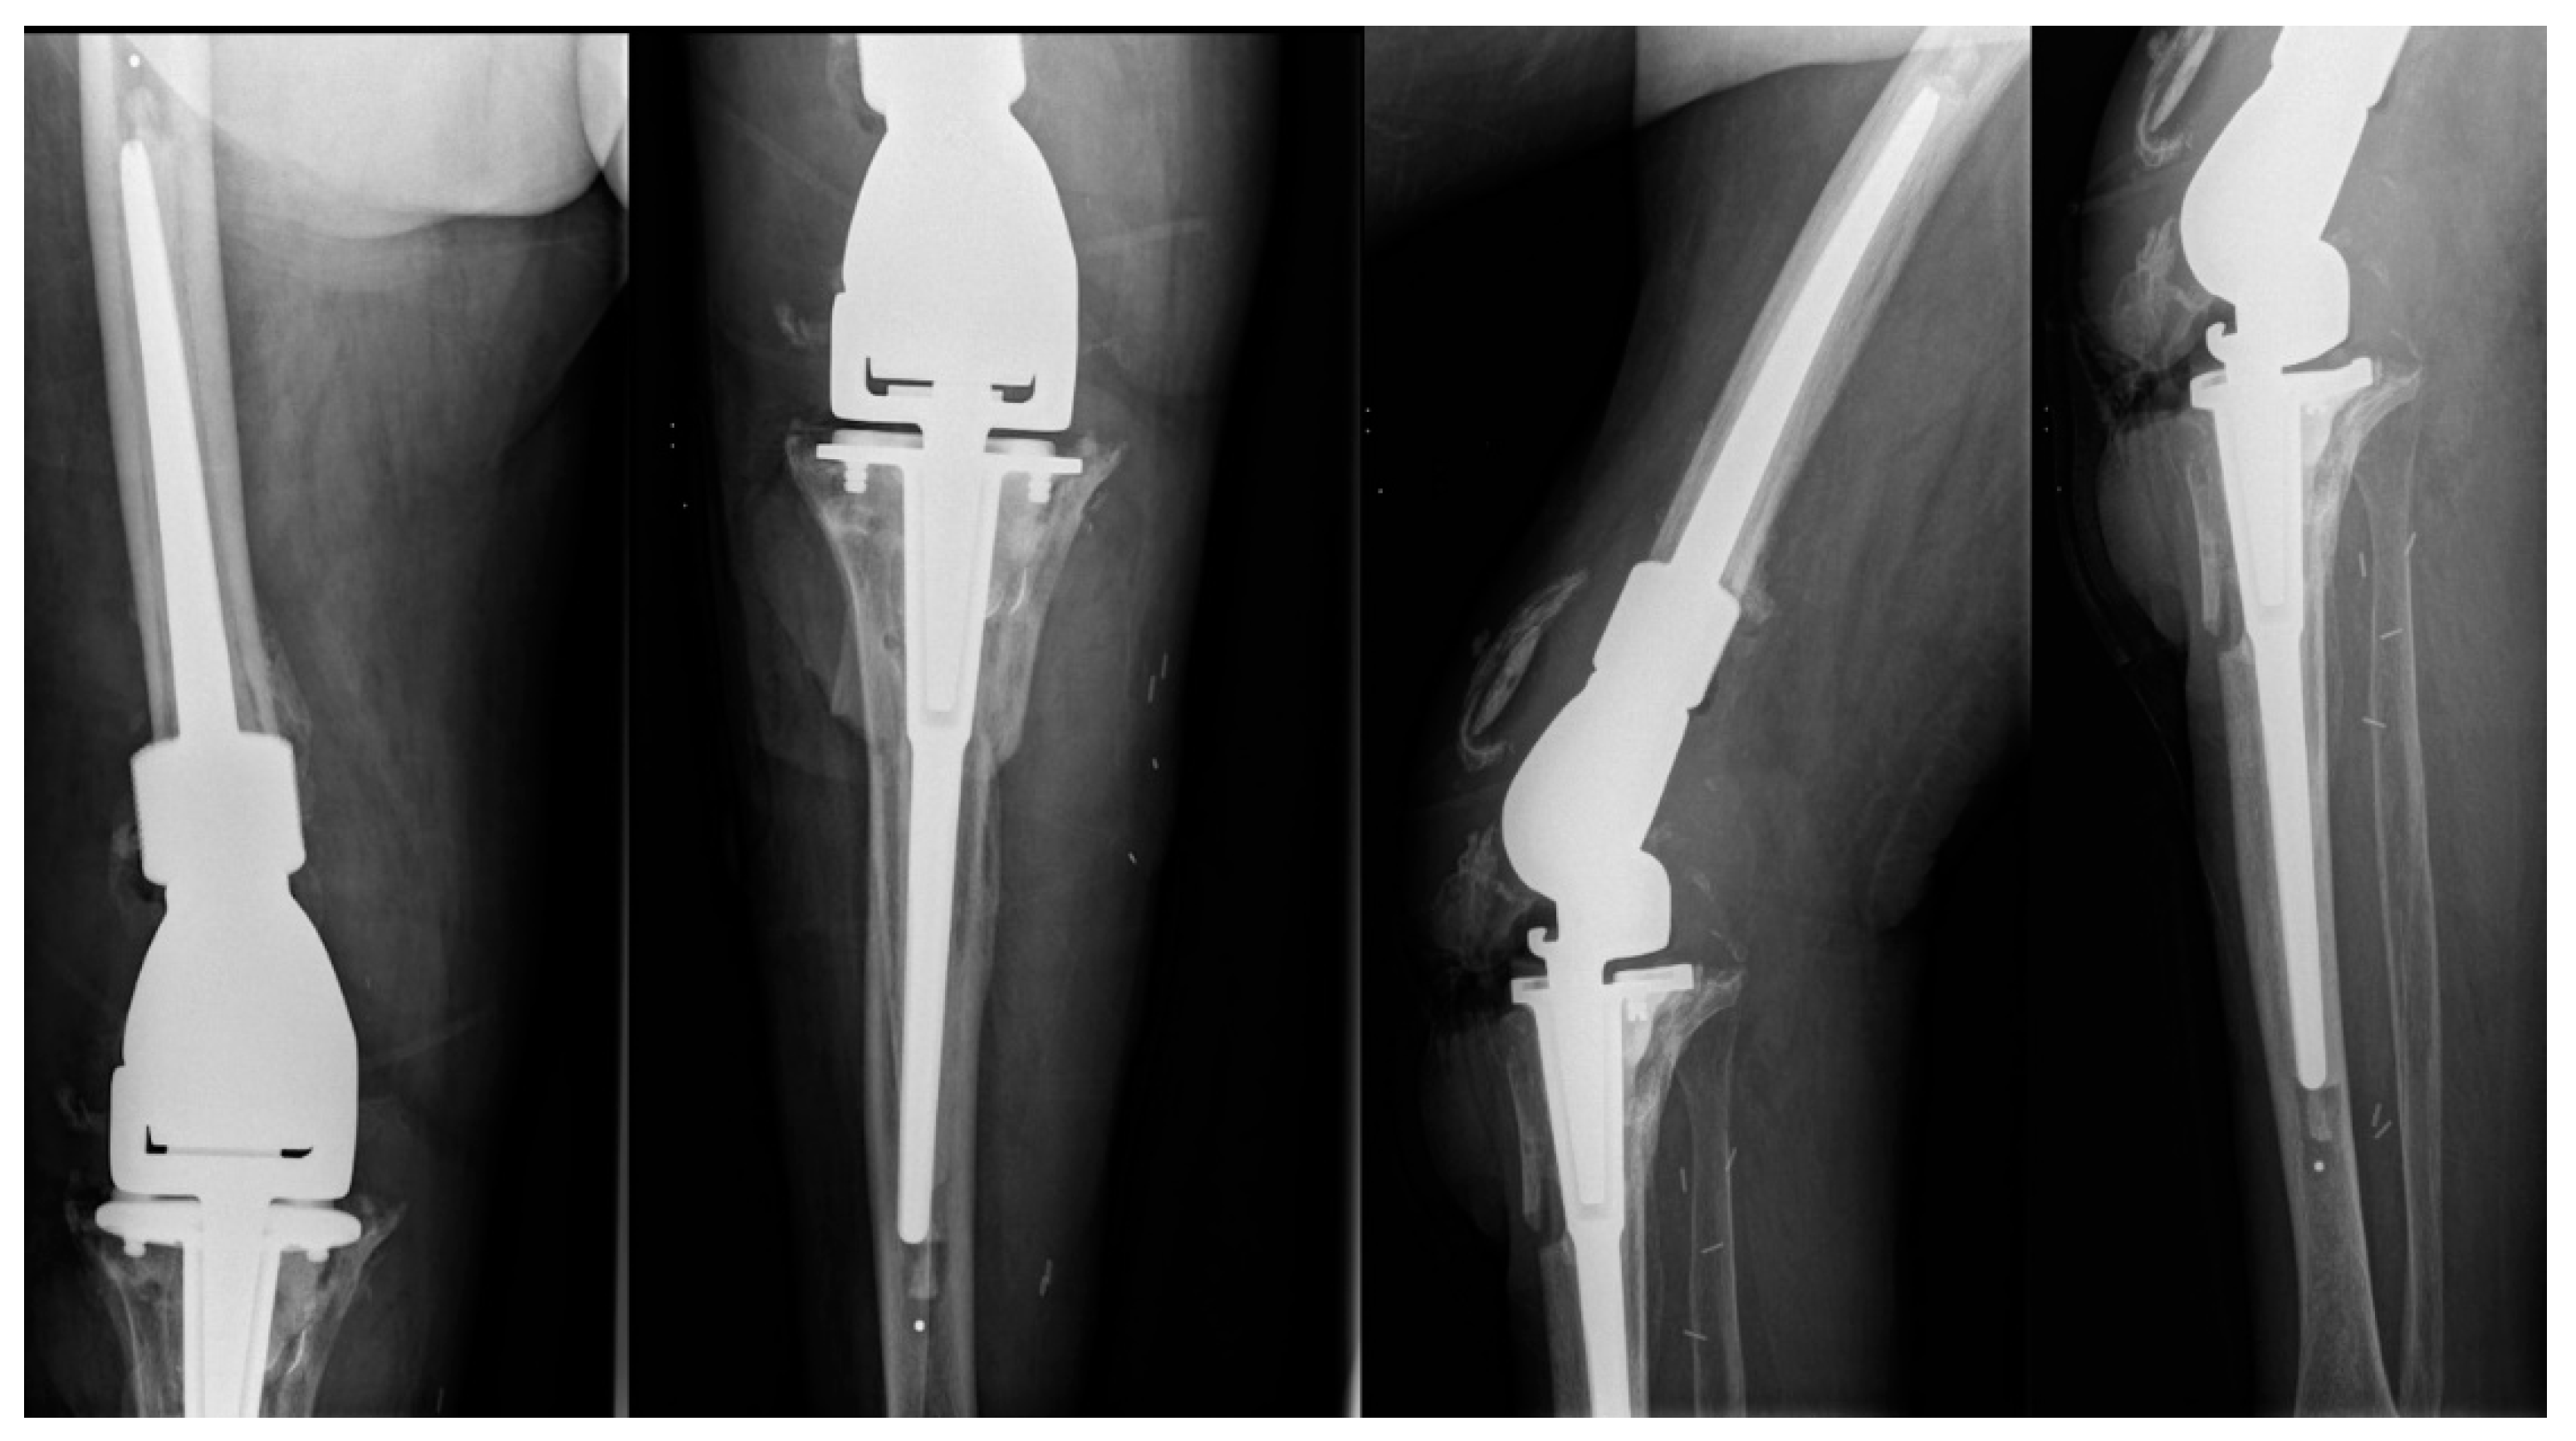

2. Case Presentation